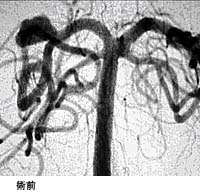

(1)破裂脳動脈瘤に対するGDC(コイル)塞栓術

*術後 コイルにより動脈瘤が写らなくなりました。